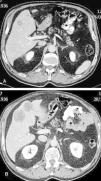

Mediante las imágenes biomédicas podemos diagnosticar, estadificar, controlar y valorar la efectividad de los procedimientos terapéuticos a los que son sometidos los pacientes oncológicos. RECIST (Response Evaluation Criteria In Solid Tumors) es el método para monitorizar el tratamiento mediante medidas unidimensionales de los tumores, obtenidas con técnicas de imagen reproducibles como son la TC, la RM y la PET. Los cambios metabólicos inducidos por los nuevos tratamientos modifican la biología y comportamiento del tumor, con discordancia ocasional entre el estado clínico del paciente y la respuesta medida con RECIST, lo que apunta a la necesidad de incluir pruebas funcionales en la valoración de la respuesta al tratamiento.

Biomedical imaging makes it possible not only to diagnose and stage cancer, but also to follow up patients and evaluate the response to treatment. RECIST (Response Evaluation Criteria In Solid Tumors) provides a method to monitor the response to treatment based on one dimensional measurements of tumors obtained with reproducible imaging techniques like CT, MRI, and PET. The metabolic changes induced by new treatments modify the biology and behavior of the tumor; occasionally, there is a discrepancy between the patient's clinical condition and the response measured by RECIST, which indicates that functional tests need to be included in the evaluation of the response to treatment.